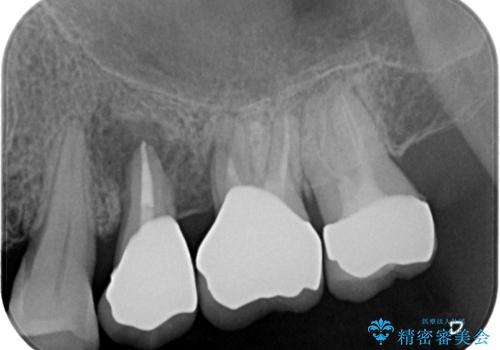

左上の奥2本は他院で根管治療と仮歯まで入れている状態です。根管治療のやり替えは希望されなかったため被せものから治療していくことにしました。

その手前の小臼歯は根尖病変が認められるため根管治療のやり直しからしていくこととしました。

左上の小臼歯は根尖病巣が大きかったため、今後も定期的にレントゲンを撮り、経過観察していく予定です。